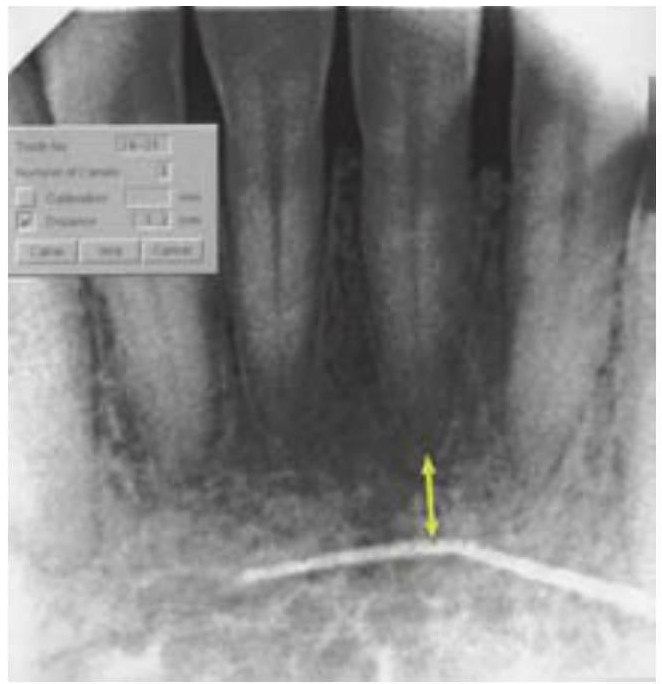

La radiología digital es un procedimiento de imagen en el cual la película es sustituida por un sensor que recoge los datos. La información analógica recibida es interpretada por un programa especializado, y se formula una imagen en la pantalla del ordenador. La imagen resultante puede ser modificada de diferentes maneras, como con la escala de grises, el brillo, el contraste, y la inversión. Se pueden formar imágenes en color para ampliar la imagen digital para una mejor evaluación. Actualmente están disponibles programas informáticos (ej. Dexislmplant) que permiten la calibración de imágenes magnificadas, además de asegurar mediciones exactas (fig. 3-2).

Al compararlos con las radiografías convencionales, los sistemas digitales más actuales tienen una significativa menor radiación con una resolución superior. En cualquier caso, con respecto a la implantología oral, la ventaja más significativa de la radiografía digital es la velocidad instantánea a la cual se forman las imágenes que es altamente útil durante la colocación quirúrgica de los implantes y la verificación de la colocación de los componentes protésicos (fig. 3-3).

Imágenes intraoperatorias

El empleo de imágenes quirúrgicas ha cambiado dramáticamente la manera en que se completa la cirugía implantológica (cuadros 3-13 y 3-14). En el pasado las desventajas de las radiografías periapicales perioperatorias han condicionado un tiempo de inefíciencia. Para verificar el posicionamiento y localización de un sitio de osteotomía o para la identificación de una estructura vital, el procesamiento de una película de radiografía estándar puede llevar hasta 6 minutos. A causa de ello, los practicantes verificaban raramente el posicionamiento de las estructuras anatómicas durante la cirugía. Con la nueva tecnología radiográfica digital se consiguen imágenes instantáneas, permitiendo completar múltiples imágenes en una fracción de tiempo. Las ventajas adicionales de las imágenes digitales intraoperatorias incluyen la manipulación de las imágenes, su calibración, mediciones exactas y el posicionamiento, y el mantenimiento de un protocolo aséptico (figs. 3-22 y 3-23).

Evaluación de los cambios de hueso alveolar

En términos radiográficos, la pérdida o falta de integración se suele indicar como una línea radiolúcida alrededor del implante. En cualquier caso, se pueden hacer falsos diagnósticos cuando el tejido blando alrededor del implante no es suficientemente amplio para superar la resolución de la modalidad radiográfica empleada. Se pueden hacer también diagnósticos positivos falsos cuando se produce el «efecto de banda de Mach» como resultado de un área de menor densidad radiográfica adyacente a un área de alta densidad (implante), lo que resulta en un área más radiolúcida que la realmente presente. En cualquier caso, los estudios han demostrado que la posibilidad de producir un efecto de banda Mach es significativamente menor con los procesados digitales de imagen. Adicionalmente, la radiografía digital ha demostrado tener la ventaja respecto de otras radiografías convencionales en relación con la «mejora del borde», que es la habilidad de detectar un espacio entre el implante y el hueso alrededor suyo (fig. 3-27).